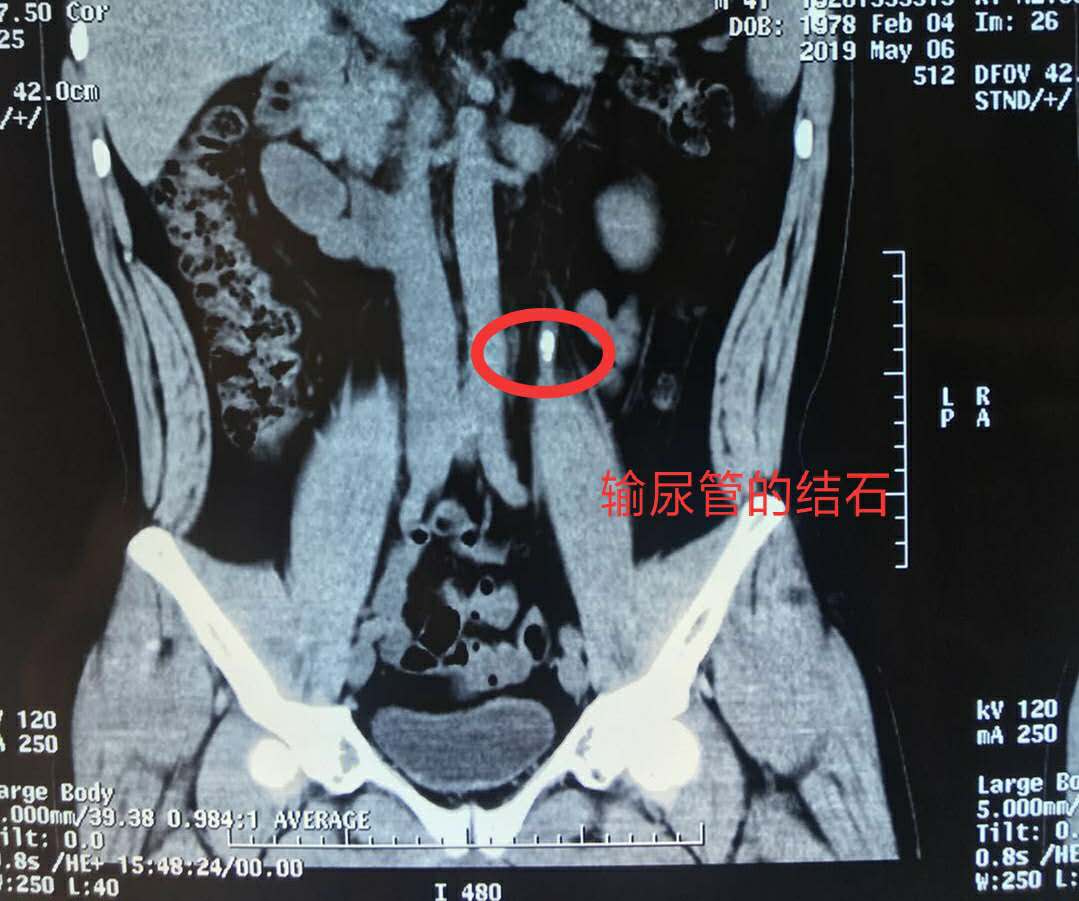

对于大多数尿路结石的病人而言,上述体外检测结石成分的方法并不适用,因为他们的结石从未离开过身体。不过,我们可以利用CT检查对体内的结石成分进行精确测量,同样能够知晓结石的真面目。